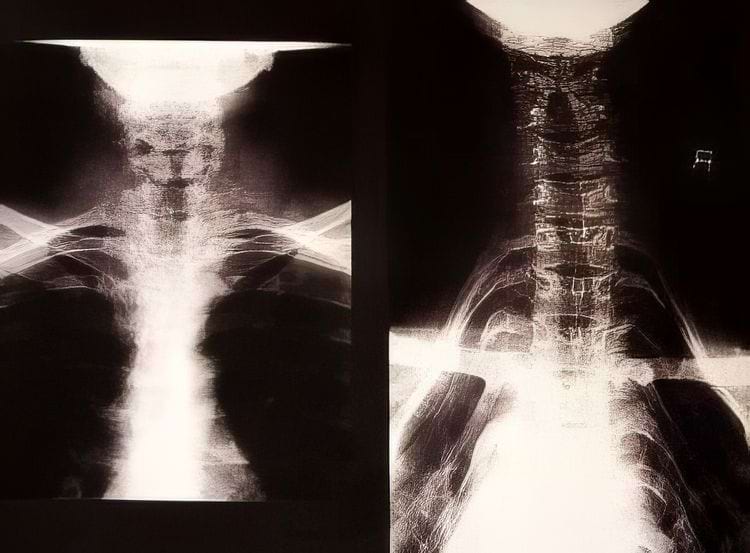

Рентгенограмма шеи женщины из племени каян в Бирме справа и обычная шея слева